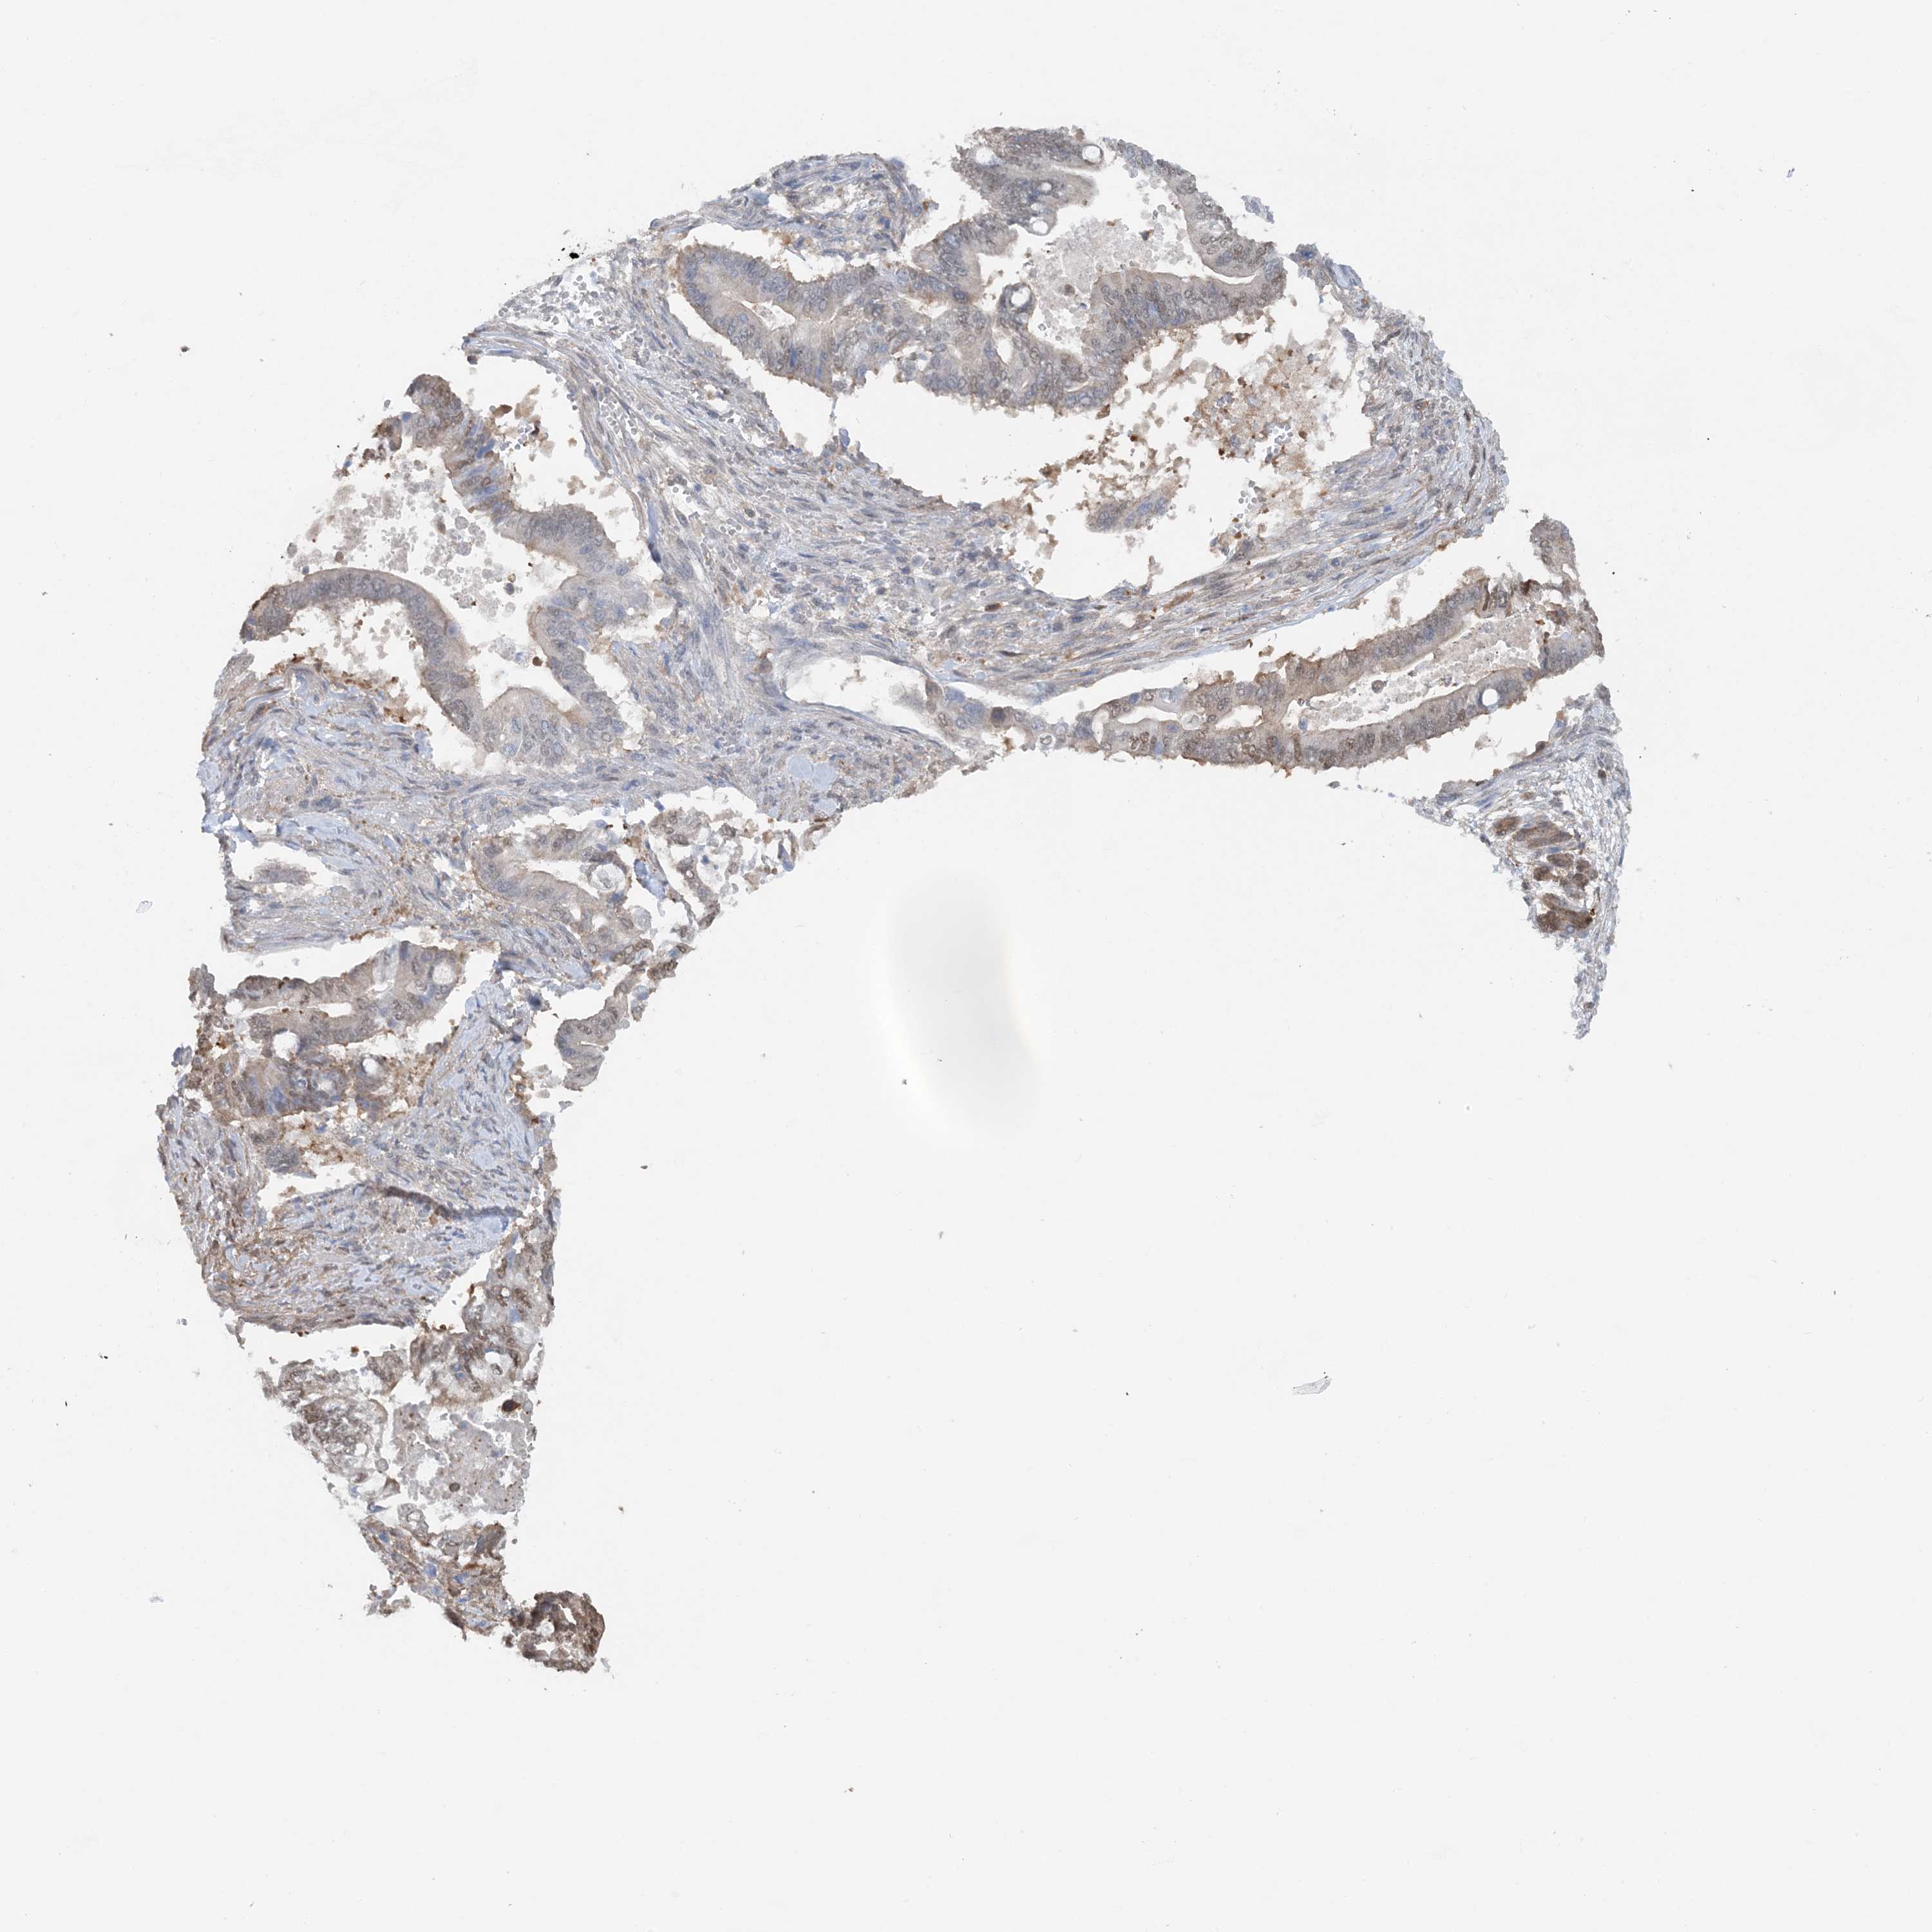

PANCREATIC CANCER - Protein expressioni

A mouse-over function shows sample information and annotation data. Click on an image to view it in a full screen mode. Samples can be filtered based on level of antibody staining by selecting one or several of the following categories: high, medium, low and not detected. The assay and annotation is described here.

Note that samples used for immunohistochemistry by the Human Protein Atlas do not correspond to samples in the TCGA dataset.

Antibody stainingi

Antibody staining in the annotated cell types in the current human tissue is reported as not detected, low, medium, or high, based on conventional immunohistochemistry profiling in selected tissues. This score is based on the combination of the staining intensity and fraction of stained cells.

Each image is clickable and will lead to virtual microscopy that enables deeper exploration of all samples and also displays staining intensity scores, fraction scores and subcellular localization as well as patient and tissue information for each sample.

Antibody HPA035063

Antibody HPA035064

Staining

High

Medium

Low

Not detected

Intensity

Strong

Moderate

Weak

Negative

Quantity

>75%

75%-25%

<25%

None

Location

Nuclear

Cytoplasmic/membranous

Cytoplasmic/membranous,nuclear

Adenocarcinoma, NOS